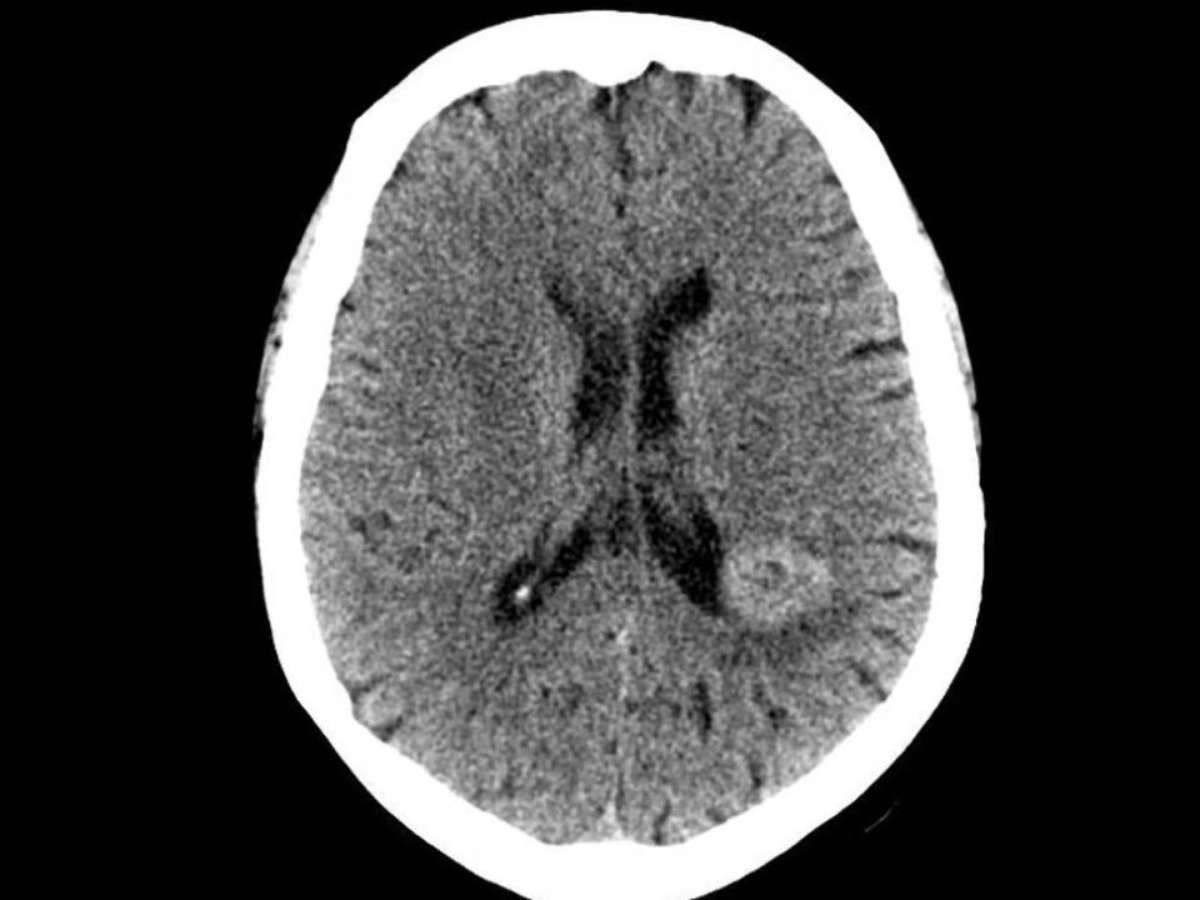

Primeiramente, tudo começou quando uma paciente de meia-idade, sem histórico psiquiátrico, passou a ouvir vozes nada familiares e persistentes. Essas pediam para ela procurar um médico e realizar um exame cerebral, isso porque afirmavam, calmamente, que ela tinha um tumor ali.

Quando contou isso aos especialistas, não recebeu atenção. Dessa forma, não quiseram que ela realizasse teste algum. Porém, as vozes continuaram, atestando que a investigação do caso era urgente. Então os médicos aceitaram a proposta para tranquilizá-la. E o resultado foi chocante. Descobriram que, realmente, ela tinha um meningioma, localizado exatamente no lugar apontado pelas mesmas.